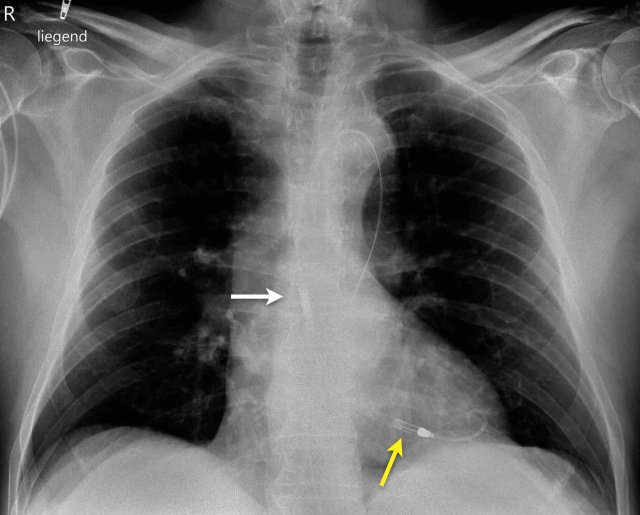

The image is taken immediately after placement of an ICD.

There is a small pneumothorax (arrow).

This is the most common complication.